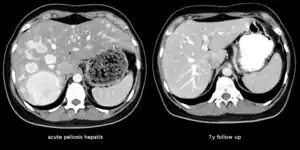

| The CT scan of a patient with peliosis hepatis (left): The follow-up CT (right) after 7 years shows full remission. | |

Peliosis hepatis is an uncommon vascular condition characterised by multiple, randomly distributed, blood-filled cavities throughout the liver. The size of the cavities usually ranges between a few millimetres and 3 cm in diameter.[1] In the past, it was a mere histological curiosity occasionally found at autopsies, but has been increasingly recognised with wide-ranging conditions from AIDS to the use of anabolic steroids. It also occasionally affects spleen, lymph nodes, lungs, kidneys, adrenal glands, bone marrow, and other parts of gastrointestinal tract.[2]

Treatment is usually directed towards management of the underlying cause. Withdrawal of azathioprine leads to remission in kidney transplant; bacillary peliosis responds to antibiotics. In rare circumstances partial resection of liver or transplant may be required.